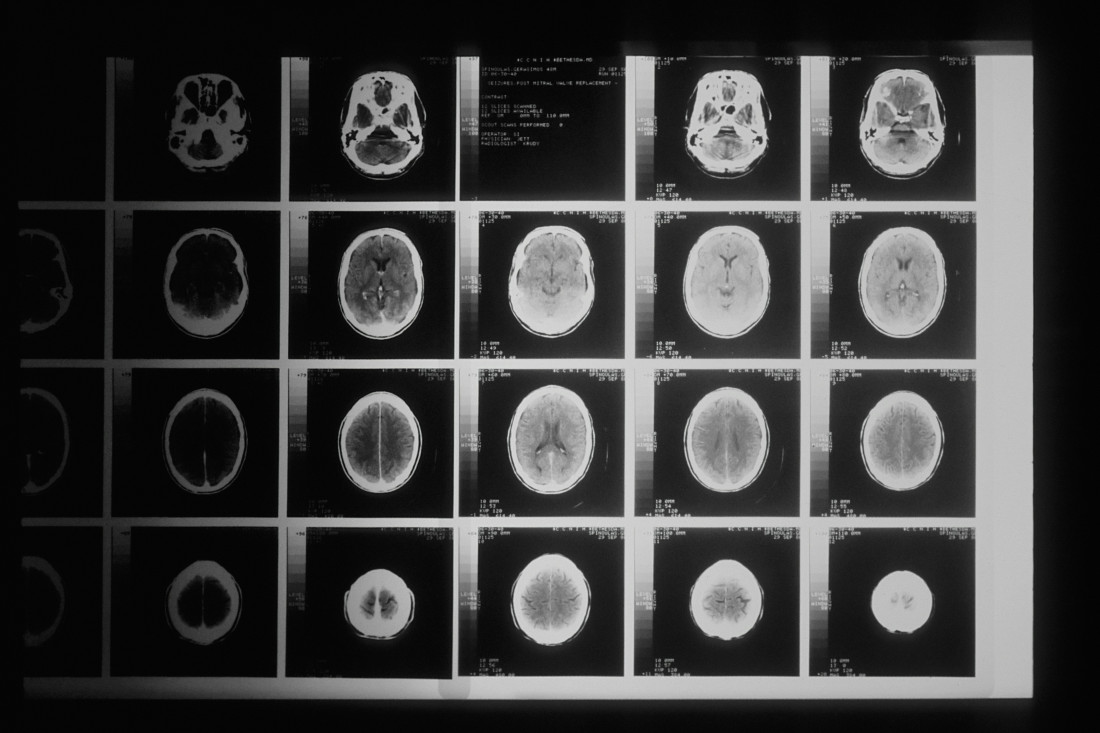

Za ovu neurološku bolest vreme je od izuzetnog značaja, a to znači da treba što pre da se postavi tačna i ispravna dijagnoza bolesti i da se pacijenti odmah adekvatno tretiraju.

Taj tretman se odnosi na primenu lekova, ali i na edukaciju pacijenata o tome kakve navike treba da imaju u životu kako bi očuvali moždano tkivo.

Istraživanja su pokazala da je primena lekova ključna u očuvanju moždanog tkiva kod obolelog pacijenta, ali i primena odgovarajućih životnih navika.

Neurolog i direktorka Univerzitetskog Kliničkog centra Srbije Jelena Drulović naglasila je da je uz podršku Ministarstva zdravlja omogućeno da pacijenti sa multiplom sklerozom imaju prioritet prilikom zakazivanja magnetne rezonance.